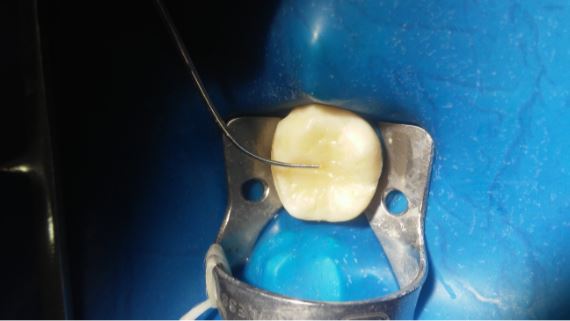

Caso clínico